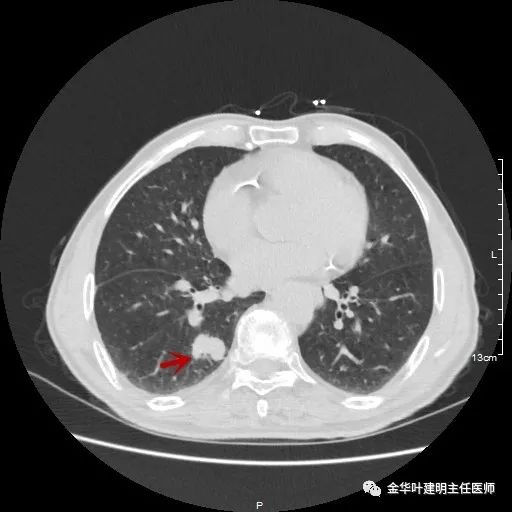

以上示右中叶病灶4。也是囊腔型病灶,病灶大,囊壁是磨玻璃密度,亦是较为典型的囊腔型肺癌影像。单病灶看,需中叶切除来治疗,因病灶3的存在,中叶切除可同时解决病灶3与病灶4。

以上示右下叶病灶5。也是主病灶,是实性块状分叶的占位性病变,基本可以肯定是肺癌。单病灶看需下叶切除并清扫淋巴结。